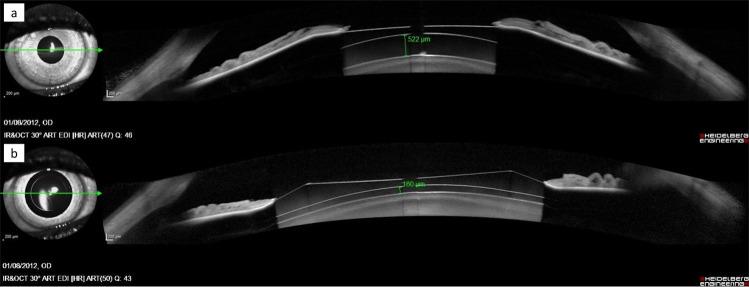

Posterior chamber phakic intraocular lens (pIOL) implantation is a common option for correcting moderate-to-high ocular refractive defects. Because this pIOL is implanted on ciliary sulcus, the distance between the back surface of the pIOL and the anterior surface of the crystalline lens, that it is known as vault, should be measured in different conditions to ensure the technique's safety. Cyclopentolate is a drug that dilates the pupil and relaxes accommodation (cycloplegia). It is often used for different ocular examinations and for other medical purposes. However, there is no evidence of the effect of this drug on vault. This study quantified central vault changes associated with cyclopentolate instillation. We measured the vault under normal conditions (pre-cycloplegic instillation) and after instilling cyclopentolate on 39 eyes of 39 patients with implanted pIOL. Our results suggest that cyclopentolate instillation may induce changes to vault in eyes with implanted pIOL. These changes seem safe and are mainly associated with vault under normal conditions, but also with anterior chamber depth, pupillary diameter and pIOL size.

后房型有晶状体眼人工晶状体(pIOL)植入术是矫正中高度眼屈光不正的常用方法。由于这种 pIOL 植入于睫状沟,因此 pIOL 后表面与晶状体前表面之间的距离,即拱高,应在不同条件下进行测量,以确保该技术的安全性。环戊通是一种散瞳和放松调节(睫状肌麻痹)的药物。它常用于不同的眼部检查和其他医疗用途。然而,目前尚无证据表明这种药物会影响拱高。本研究定量评估了与环戊通滴眼相关的中央拱高变化。我们在 39 例植入 pIOL 的患者的 39 只眼中,分别测量了正常状态(未散瞳滴眼前)和滴入环戊通后的拱高。我们的结果表明,环戊通滴眼可能会引起植入 pIOL 眼的拱高变化。这些变化似乎是安全的,主要与正常状态下的拱高有关,但也与前房深度、瞳孔直径和 pIOL 大小有关。